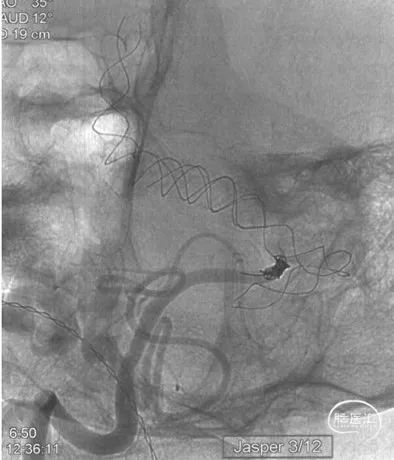

Jasper 3mm/12cm弹簧圈一枚

导引导管超选至右侧椎动脉,在右椎汇入处填入Jasper 3/12弹簧圈一枚,造影可见右椎汇合处血流阻断